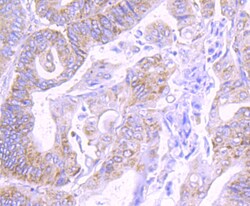

COX4 Polyclonal Antibody for Western Blot, ICC/IF, IHC (P), Flow

| Flow Cytometry, Immunohistochemistry (Paraffin), Western Blot, Immunocytochemistry | |